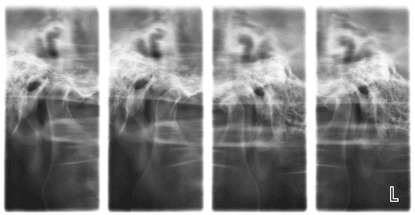

Темпоромандибуларни стави (TMJ)

Тази рентгенова снимка показва темпоромандибуларните стави, с които долната челюст е подвижно свързана с черепа. Образът дава възможност да се направи сравнение между лявата и дясната става, които са заснети в отворено и затворено положение на устата. Прави се при проблеми и нужда от лечение на дъвкателния апарат.